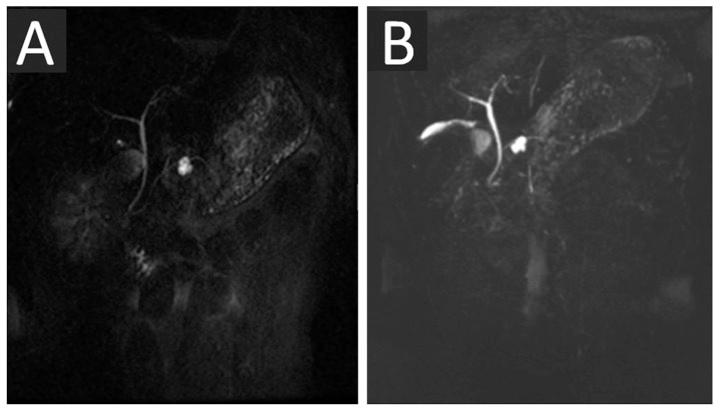

The present study aimed to compare two-dimensional (2D) and three-dimensional (3D) magnetic resonance cholangiopancreatography (MRCP) for the assessment of pancreatic cystic lesions. Between February 2009 and December 2011, 35 patients that had been diagnosed with pancreatic cystic lesions, which was confirmed by surgery and pathology, underwent pre-operative 2D or 3D MRCP for pre-operative evaluation. In the present study, the quality of these 2D and 3D MRCP images, the visualization of the features of the cystic lesions, visualization of the pancreatic main duct and prediction of ductal communication with the cystic lesions were evaluated and compared using statistical software. The 3D MRCP images were determined to be of higher quality compared with the 2D MRCP images. The features of the cystic lesions were visualized better on 3D MRCP compared with 2D MRCP. The same capability for the visualization of the segment of the pancreatic main duct was exhibited by 3D and 2D MRCP. There was no significant difference between the area under the receiver operating characteristic curve values of 2D and 3D MRCP, which assessed the prediction of communication between cystic lesions and the pancreatic main duct. It was concluded that, compared with 2D MRCP, 3D MRCP provides an improved assessment of pancreatic cystic lesions, but does not exhibit an improved capability for the visualization of the pancreatic main duct or for the prediction of communication between cystic lesions and the pancreatic main duct.

本研究旨在比较二维(2D)和三维(3D)磁共振胰胆管造影(MRCP)对胰腺囊性病变的评估效果。2009年2月至2011年12月期间,35例经手术及病理确诊为胰腺囊性病变的患者接受了术前2D或3D MRCP检查以进行术前评估。在本研究中,使用统计软件对这些2D和3D MRCP图像的质量、囊性病变特征的可视化、胰腺主导管的可视化以及导管与囊性病变相通的预测情况进行了评估和比较。结果显示,与2D MRCP图像相比,3D MRCP图像质量更高。与2D MRCP相比,3D MRCP能更好地显示囊性病变的特征。2D和3D MRCP对胰腺主导管节段的可视化能力相同。在评估囊性病变与胰腺主导管相通的预测方面,2D和3D MRCP的受试者操作特征曲线下面积值无显著差异。研究得出结论,与2D MRCP相比,3D MRCP能更好地评估胰腺囊性病变,但在胰腺主导管可视化或囊性病变与胰腺主导管相通预测方面并无改进。